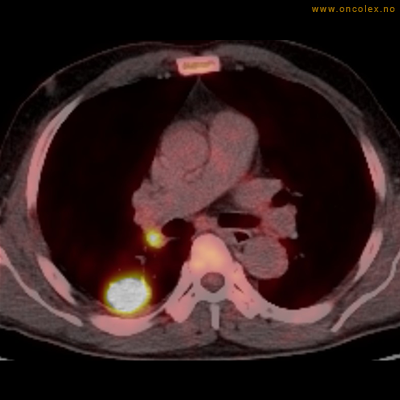

Vev som tar opp mer radioaktivt stoff, synes som hvite områder som lyser opp mer i forhold til annet vev som tar opp mindre sukker.

Kraftig opptak i svulst i lunge.

Lungekreft med spredning til lymfeknute i lungehilus.

Adenokarsinom distalt i spiserør. Fysiologisk opptak i hjertemuskulatur.